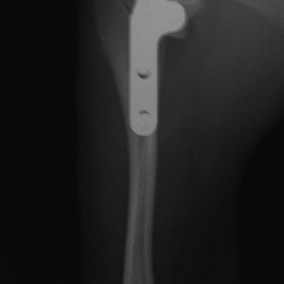

バーニーズマウンテンドック 4歳 避妊♀

突然の右後肢跛行を主訴に来院されました。整形外科学的検査において右膝に脛骨圧迫テストで陽性、前方引き出し徴候が認められました。神経学的検査において特に異常は認められませんでした。レントゲン検査において、関節液の貯留所見や脛骨の前方変位の所見が認められました。

関節鏡検査を実施いたしました。関節鏡検査では、重度の滑膜炎および前十字靭帯の完全断裂が認められました。半月板に損傷は認められませんでした。

断裂前十字靭帯の除去を行いました。その後 TTA(Tibial tuberosity advancement)を実施しました。

術後経過は良好で、後肢機能・筋肉量の改善目的で現在はリハビリテーションを行っています。